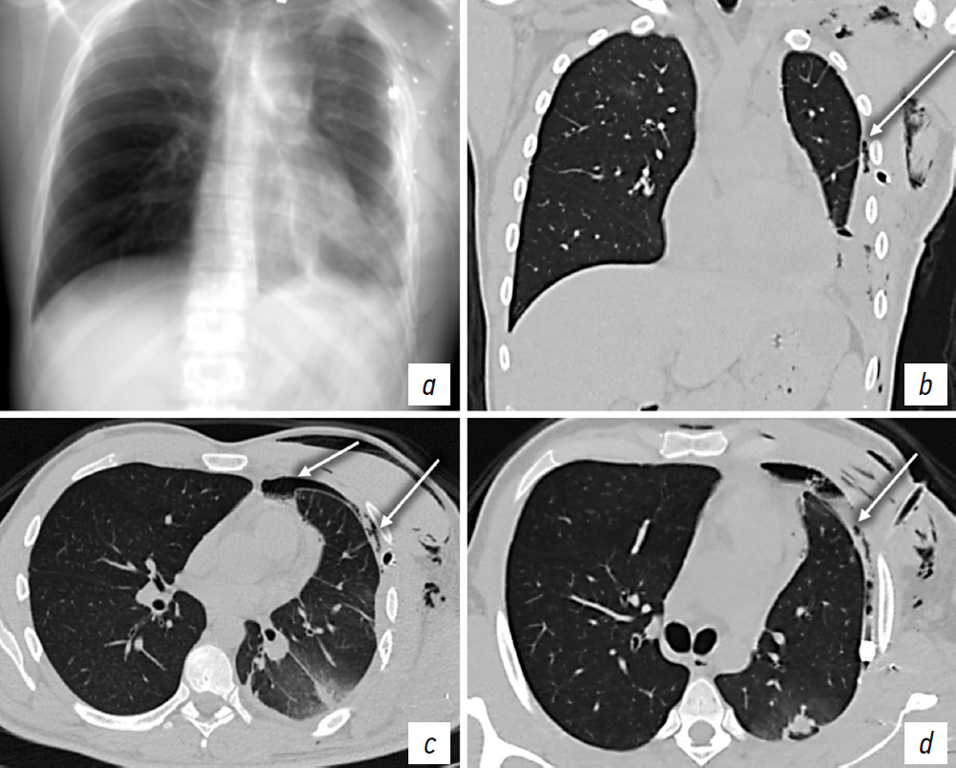

In all eight false-positive cases of pneumothorax, specific CT features were identified. A thin collection of air was noted between the inner surface of the thoracic cage and lungs, predominantly in the mid- and basal zones, with a heterogeneous structure caused by multiple septations of varying thickness and morphology and areas of fat density (–100 to –80 HU). These findings were consistent with subcutaneous emphysema but with an atypical location, within the thoracic cavity projection. On radiograph, the patients exhibited a well-defined radiolucent band between the chest wall and lung margin (Fig. 3).

Fig. 3. Patient M. a, chest X-ray in the anteroposterior view. Chest CT: b, coronal plane; c, d, axial plane at different levels. Pneumomediastinum. Extrapleural emphysema on the right (arrows).

Рис. 3. Пациент М. a — рентгенограмма органов груди в прямой проекции. КТ органов груди: b — фронтальная плоскость; c, d — аксиальная плоскость на разных уровнях. Пневмомедиастинум. Эмфизема ЭПП справа (стрелки).